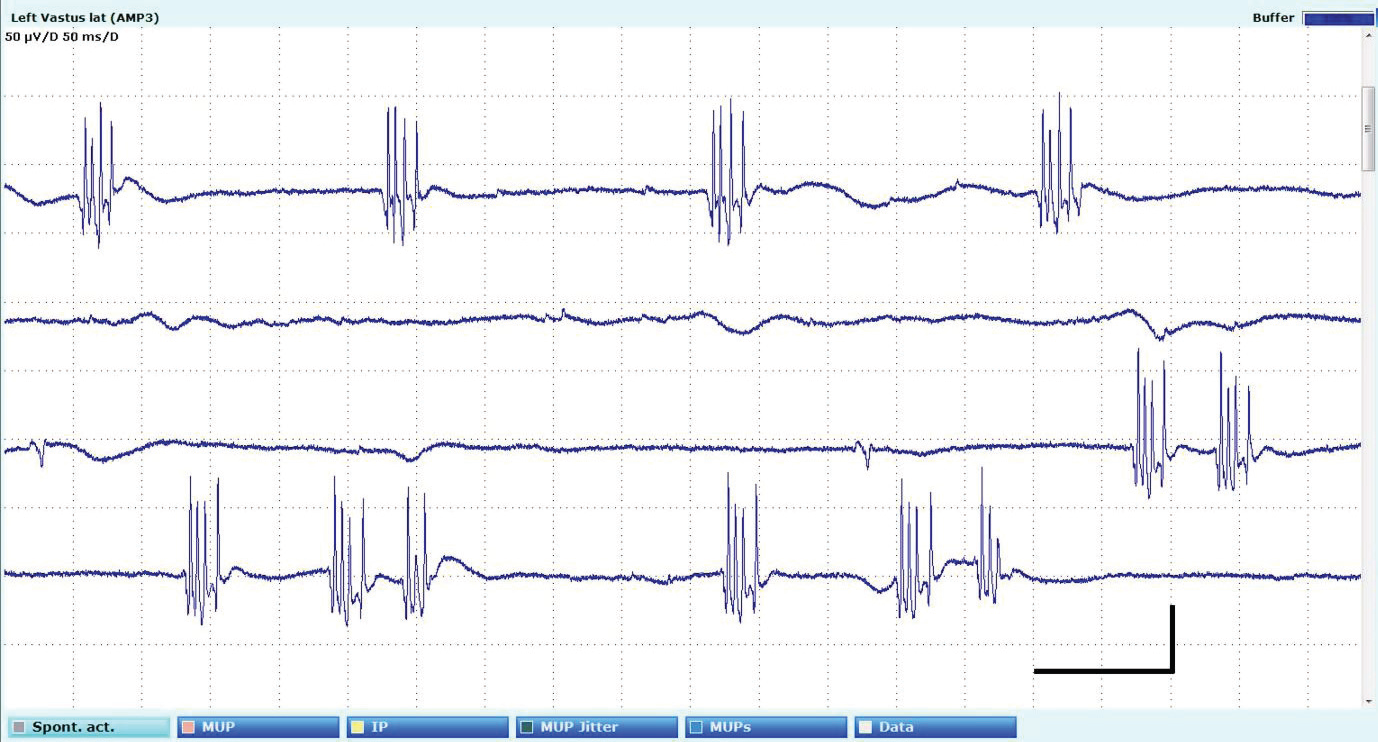

due to the after-discharges.[Figure 2] Electromyography revealed

myokymic discharges, sparse fasciculations and complex motor unit

potentials in limb and paraspinal muscles.[Figure 3] Mixed nerve and

Figure 3:Needle electromyography in tibialis anterior depicting myokymic discharges. Sensitivity 50uV/d, sweep duration 1 second.

hyperexcitability can be demonstrated with motor nerve conduction

study which reveal repetitive after-discharges following the compound

muscle action potential, often obscuring the F-wave. Needle EMG

reveals myokymia, complex motor unit potentials and neuromyotonia.